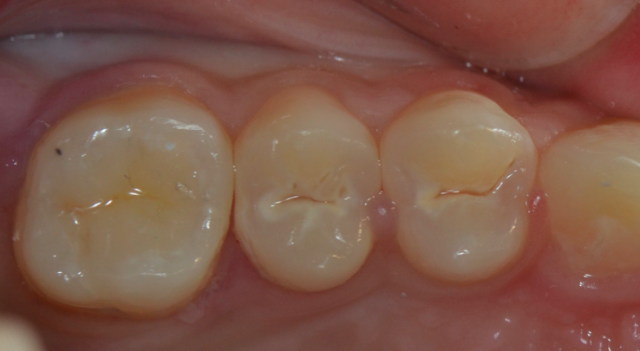

術(shù)后即刻照

20151112162536_64068.png

術(shù)前術(shù)后對比

20151112162632_45798.png